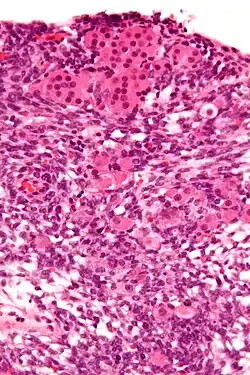

Das Androblastom [Etymologie: griechisch ἀνδρὀς = Mann und Blastom] (Syn. Arrhenoblastom; griechisch ἅρρην = Mann) ist ein sehr seltener Tumor der Keimdrüsen, der sowohl bei Männern im Hoden als auch bei Frauen im Eierstock auftreten kann. Es handelt sich um Tumoren, die von den Sertoli-Zellen, den Leydig-Zwischenzellen oder von beiden ausgehen können. Sie können hoch- oder mittelgradig differenziert, aber auch sarkomartig entdifferenziert vorkommen. Häufig treten auch bis zu 20 % Komponenten anderer (heterologer) Gewebe (Knorpel, Skelettmuskulatur, mukoide Magen-Darm-Epithelien) auf.[1] Bei hohem Leydig-Anteil zeigt sich aufgrund der Testosteronbildung bei Frauen eine Virilisierung mit androgenem Zellbild in der Vaginalzytologie.[2]